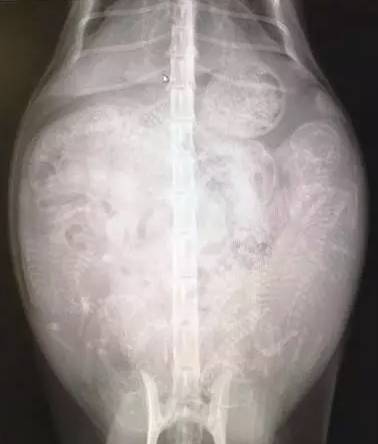

3、猫妈腹部逐渐涨大,此时不要进行腹部触诊,这样可能会造成胎儿的严重伤害。当然,受过专业训练的兽医可以这样进行检查。

如何分辨母猫是否难产?

1、外阴部有异常的分泌物(如红绿色分泌物且有恶臭)

2、母猫叫虚弱,不规律地腹部用力超过2~4个小时

3、在外阴部可以看见小猫或者囊泡,超过15分钟还没将小猫生出来

4、羊膜破掉且羊水流出,但小猫却没生出来

5、母猫一直哭叫和舔咬阴部

6、超过预产期一周以上还没生

7、无法在36个小时内将所有小猫咪生出来